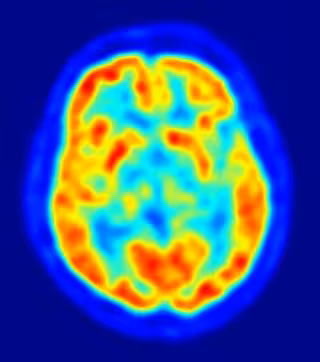

cerebro, recurso, neuronas

Foto: JENS LANGNER